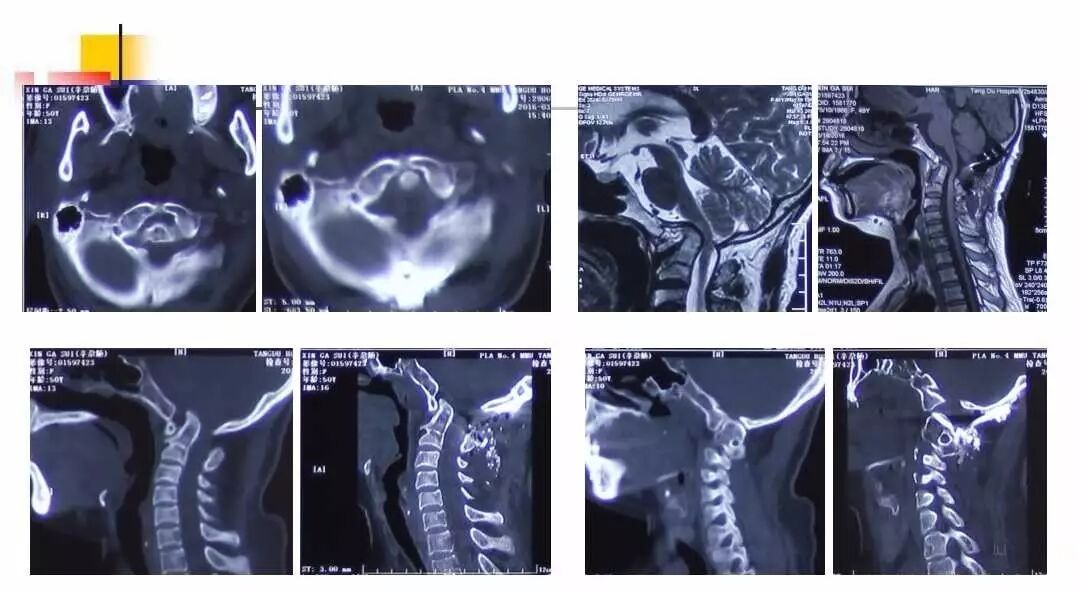

在脊柱神经外科、显微神经外科和颅底肿瘤外科前沿研究和临床诊治领域有着扎实的基础,为全国首批获得脊柱神经外科医师培训认证的神经外科医生。擅长颈椎病、椎管肿瘤及各种脊柱疑难疾病的诊治、脑肿瘤微创手术,尤其擅长颈椎退行性疾病的手术,率先在国内开展了颅底凹陷后路复位、颈前路减压融合等高难度手术,多年来收治了来自全国各地的大量患者,疗效达到国内领先水平。